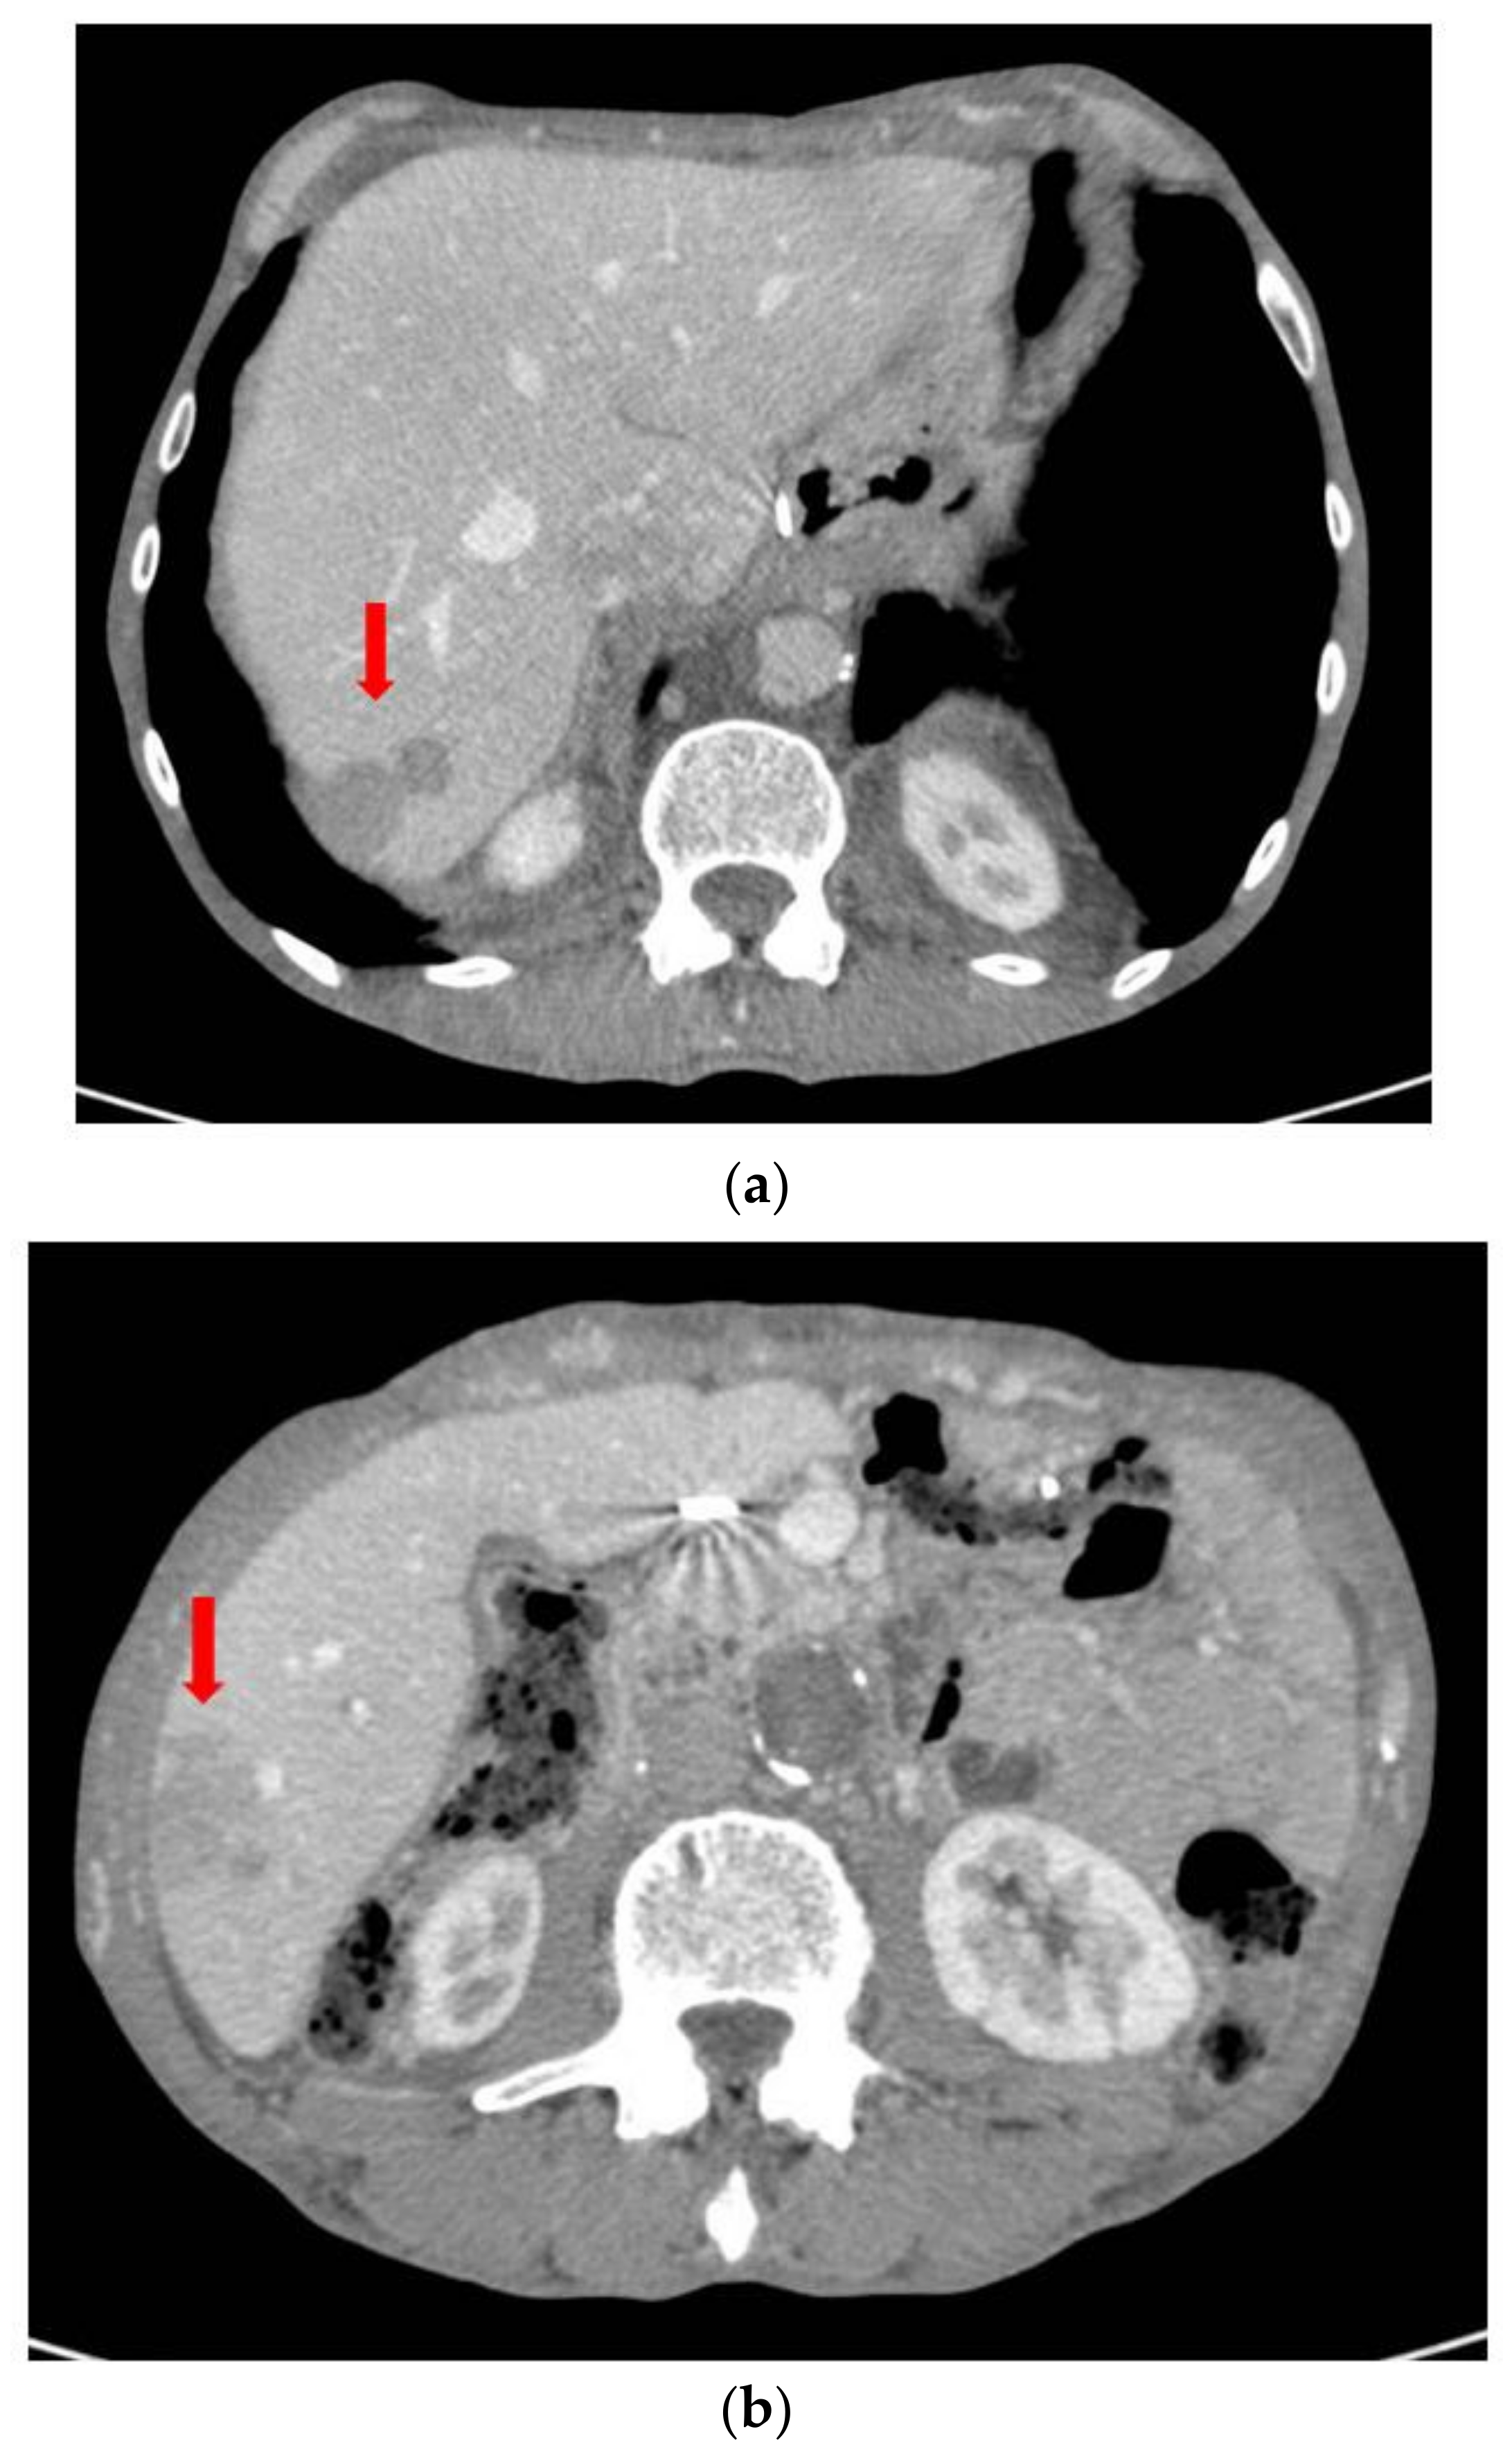

2. Case Report

3. Discussion and Literary Review